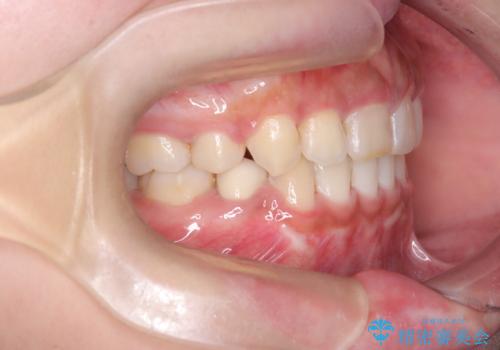

前歯の突出感を改善|上下4本の抜歯と審美ワイヤー矯正でバランスの取れた口元へ

- 患者様は、前歯の突出感を気にされて来院されました。診察の結果、歯列のスペースが不足しており、前歯を後方へ移動させるには抜歯が必要と判断。上下の小臼歯4本を抜歯し、目立ちにくい審美ワイヤー矯正(白いワイヤーと透明ブラケット)を使用して治療を行う計画を立てました。

抜歯によって前歯を下げるためのスペースを確保。その後、審美ワイヤー矯正を用いて、歯列全体のバランスを整えながら前歯を後方へ移動させました。治療後は、横顔のラインが整い、自然な口元になったことで、見た目も噛み合わせも改善しました。患者様からは「口元がすっきりして、自信を持って笑えるようになった」と喜びの声をいただきました。